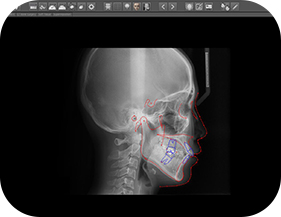

모르페우스란 3D 실측 데이터를 체계적으로 활용한 시뮬레이션으로 정면과 측면을 촬영하고 엑스레이(Ceph)사진을 도입하여 교정 전/후를 비교할 수 있는 가상 3D 시뮬레이션 장비입니다.